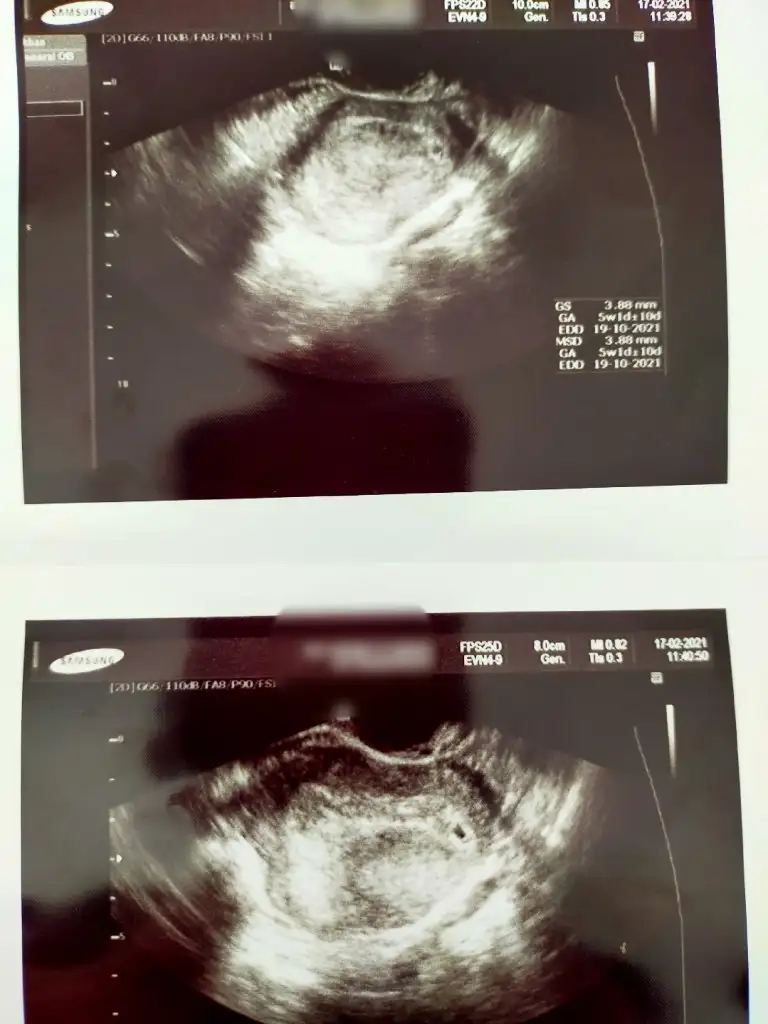

Sat 01 Ocak ona göre 7+0 olmaliydi bugun dünkü kese fotosunu da önceki günüde atayım bı fark varmı bakBetanın önemi yok derken, kese göründükten sonra o takip edilir demek oluyor. 5+2 ultrasonda olan. Pekii adetine göre dün kaç olması gerekiyordu canım?

Vajinalmi bakildi kese ?Sat 01 Ocak ona göre 7+0 olmaliydi bugun dünkü kese fotosunu da önceki günüde atayım bı fark varmı bak

Evet canım vajinalVajinalmi bakildi kese ?